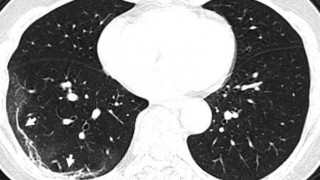

Κορωνοϊός: Ανατριχιαστική ακτινογραφία ασθενούς

Metrosport Team

12.03.2020